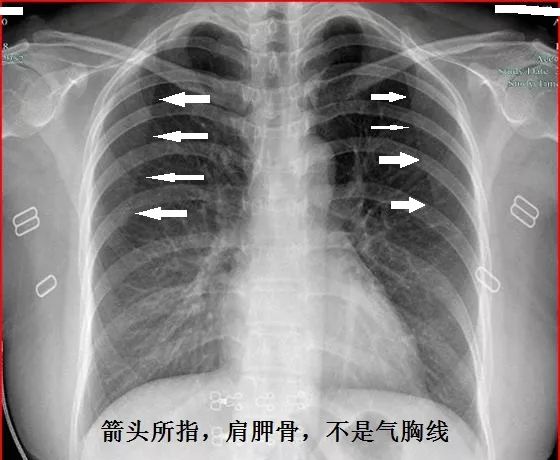

顺便说说,胸片诊断气胸,一定要会分辨肺纹理。肺纹理消失的地方,才考虑气胸,不可看见肩胛线就误以为是气胸。